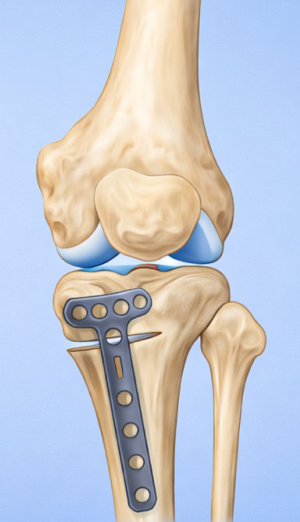

정강이 위쪽 뼈(경골 근위부)를 절골합니다.

약간 벌리거나 닫아서 다리축을 “일자에 가깝게” 교정해서 닳은 안쪽 무릎의 부담을 줄이고 통증 감소 및 기능 향상을 유도합니다.

절골한 부위는 금속판(plate)으로 고정합니다.

시간이 지나면 뼈가 붙습니다.